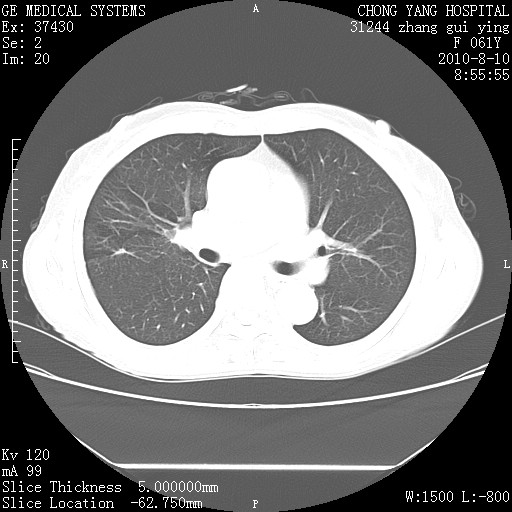

标题: CT28314:F61Y胸部增强,发热咳嗽一周入院,后面的为一周前平

右肺下叶中心性肺癌可能性大

1、支持考虑右侧中央型肺癌伴右肺中叶节段性不张及下叶支气管黏液痰栓    2、左肺上叶舌段感染。

支持右下肺中央型肺癌并左上肺感染.

我也觉得右肺中叶支气管受累

支持3楼意见,还要考虑:纵隔及肺门淋巴结转移、右侧少量胸腔积液。

支持考虑右侧中央型肺癌

确切的说:1:右肺下叶中心型肺癌侵及中叶支气管并中叶不张,纵膈淋巴结转移。2:左肺舌叶炎症。3:右侧胸腔少量积液

块影平扫32hu,动静脉期62-70hu.

右肺下叶内基底段近膈不规则肿块,考虑右肺下叶周围型肺癌可能性大。

考虑右下肺肺癌,纵隔淋巴结转移i。